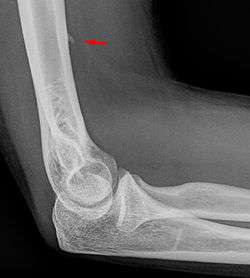

Larger supracondylar process seen on a lateral radiograph of the elbow

The supracondylar process of the humerus is a bony projection on the anteromedial aspect of the upper arm bone (humerus), about 5 cm above the medial epicondyle. It is directed downward, forward and medially pointing to the medial epicondyle. It is an anatomical variation which occurs in about one percent of all people. A fibrous band, Struthers ligament, may connect this process to the medial epicondyle.

Supracondylar processes are usually asymptomatic, but may be palpable as a mass on the upper arm. They are most commonly found as an incidental finding on radiographs made for other reasons, but occasionally isolated fractures of the process itself may lead to its discovery. Rarely, presence of the process and a connecting ligament may lead to compression of the brachial artery and the median nerve, leading to pain, paresthesia and/or ischemia.